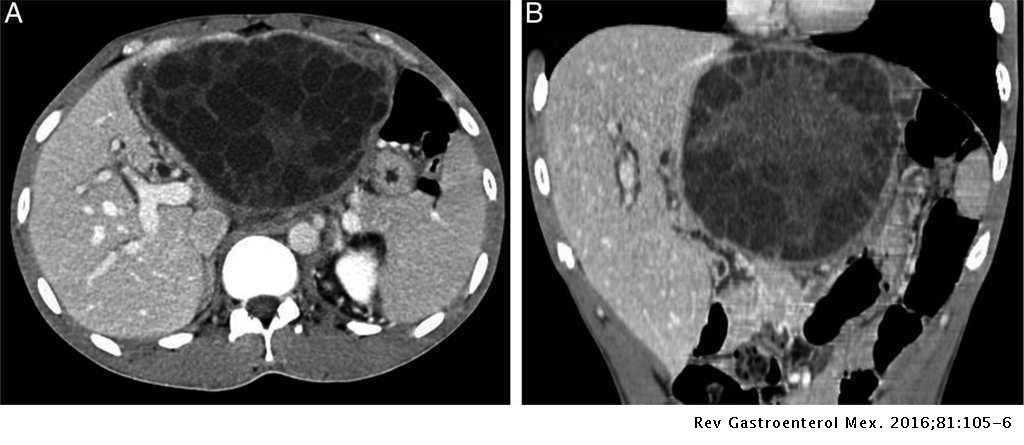

hemangioma

hemangioma: mais comum, hiperproliferação vascular

us com lesão homogêna e hipoecóica

tc: enchimento precoce da perifeira padrão centripeto wash-in (globuliforme). Na fase tardia, lesão hiperintensa (no adenoma é hipodensa)

T1: hipointenso

T2: hiperintenso em relação ao parênquima hepático, mas menos intenso que o liquor

T1 com gadolíneo: realce periférico nodular descontínuo que progride de forma centrípeta nas imagens tardias

T1 com contraste hepatoespecífico: apresentam uma ampla gama de aparências, tornando esse método menos útil.

Na fase hepatoespecífica, pode apresentar pseudo-washout (aumento da captaçaõ de contraste pelo parênquima hepático adjacente)